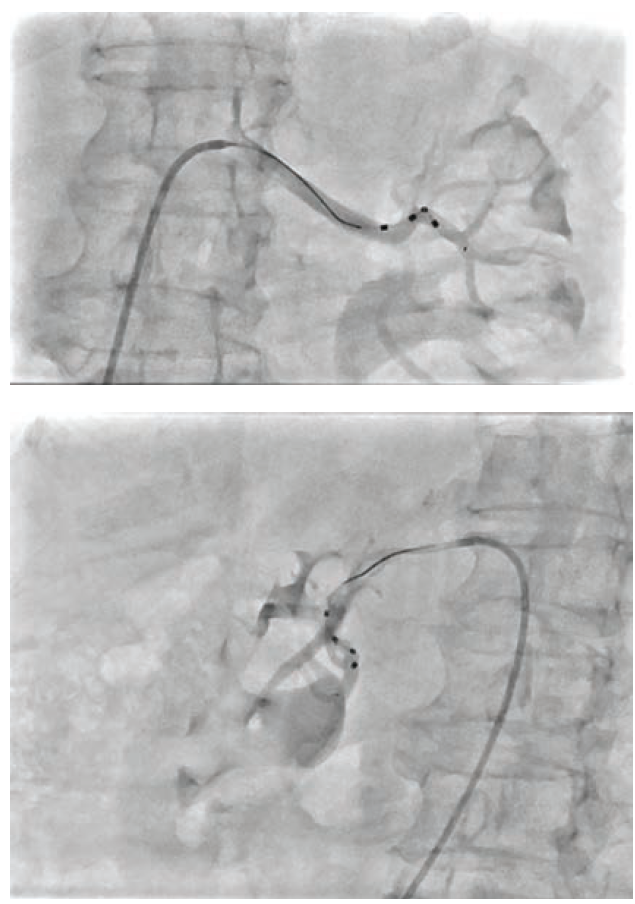

You mentioned avoiding lesions that are greater than 50%. How is that disease handled if a patient otherwise meets the criteria for renal denervation?

All our patients will get anatomical imaging as part of their secondary evaluation in our hypertension center. We usually do this with a duplex ultrasound, but sometimes we need more axial imaging like a computed tomography angiography (CTA) or magnetic resonance angiography (MRA). Most often from these studies we can determine next steps, but sometimes it is a staged approach if renal artery stenosis is suspected. For instance, I recently had a patient with severe resistant hypertension. He had gone up to 5 anti-hypertensive medications and was using breakthrough hydralazine during the day. His duplex ultrasound showed fairly normal renal artery velocities, but an MRA suggested there might be some ostial disease on his right kidney artery. He also had stage 2 chronic kidney disease. We discussed in clinic that we needed to do something for his blood pressure and have two potential options. First, if the right renal artery is diseased, we can consider a renal stent and then can re-evaluate his blood pressure response with this intervention. However, if the right renal artery is not severely diseased, meaning we don’t see a severe lesion or have a significant pressure drop across the lesion, then we have the opportunity to still do renal denervation. He agreed, and we brought this patient to the cath lab and did an angiogram. We found very severe right ostial renal disease and put in a renal stent. We are now following him back in clinic. With the Spyral RDN system, we can still do RDN as long as it is >90 days after renal stenting. Our plan is to see how his blood pressure responds, and if we are still not at goal, we can then consider RDN. It was a great conversation to have with the patient, where I was able to offer a couple ways to improve his blood pressure control and make his daily life more livable. It is an elective procedure and the patient has to feel involved in the decision making, but if we can do this safely and in a way that is least burdensome to the patient, I think it is a great win.